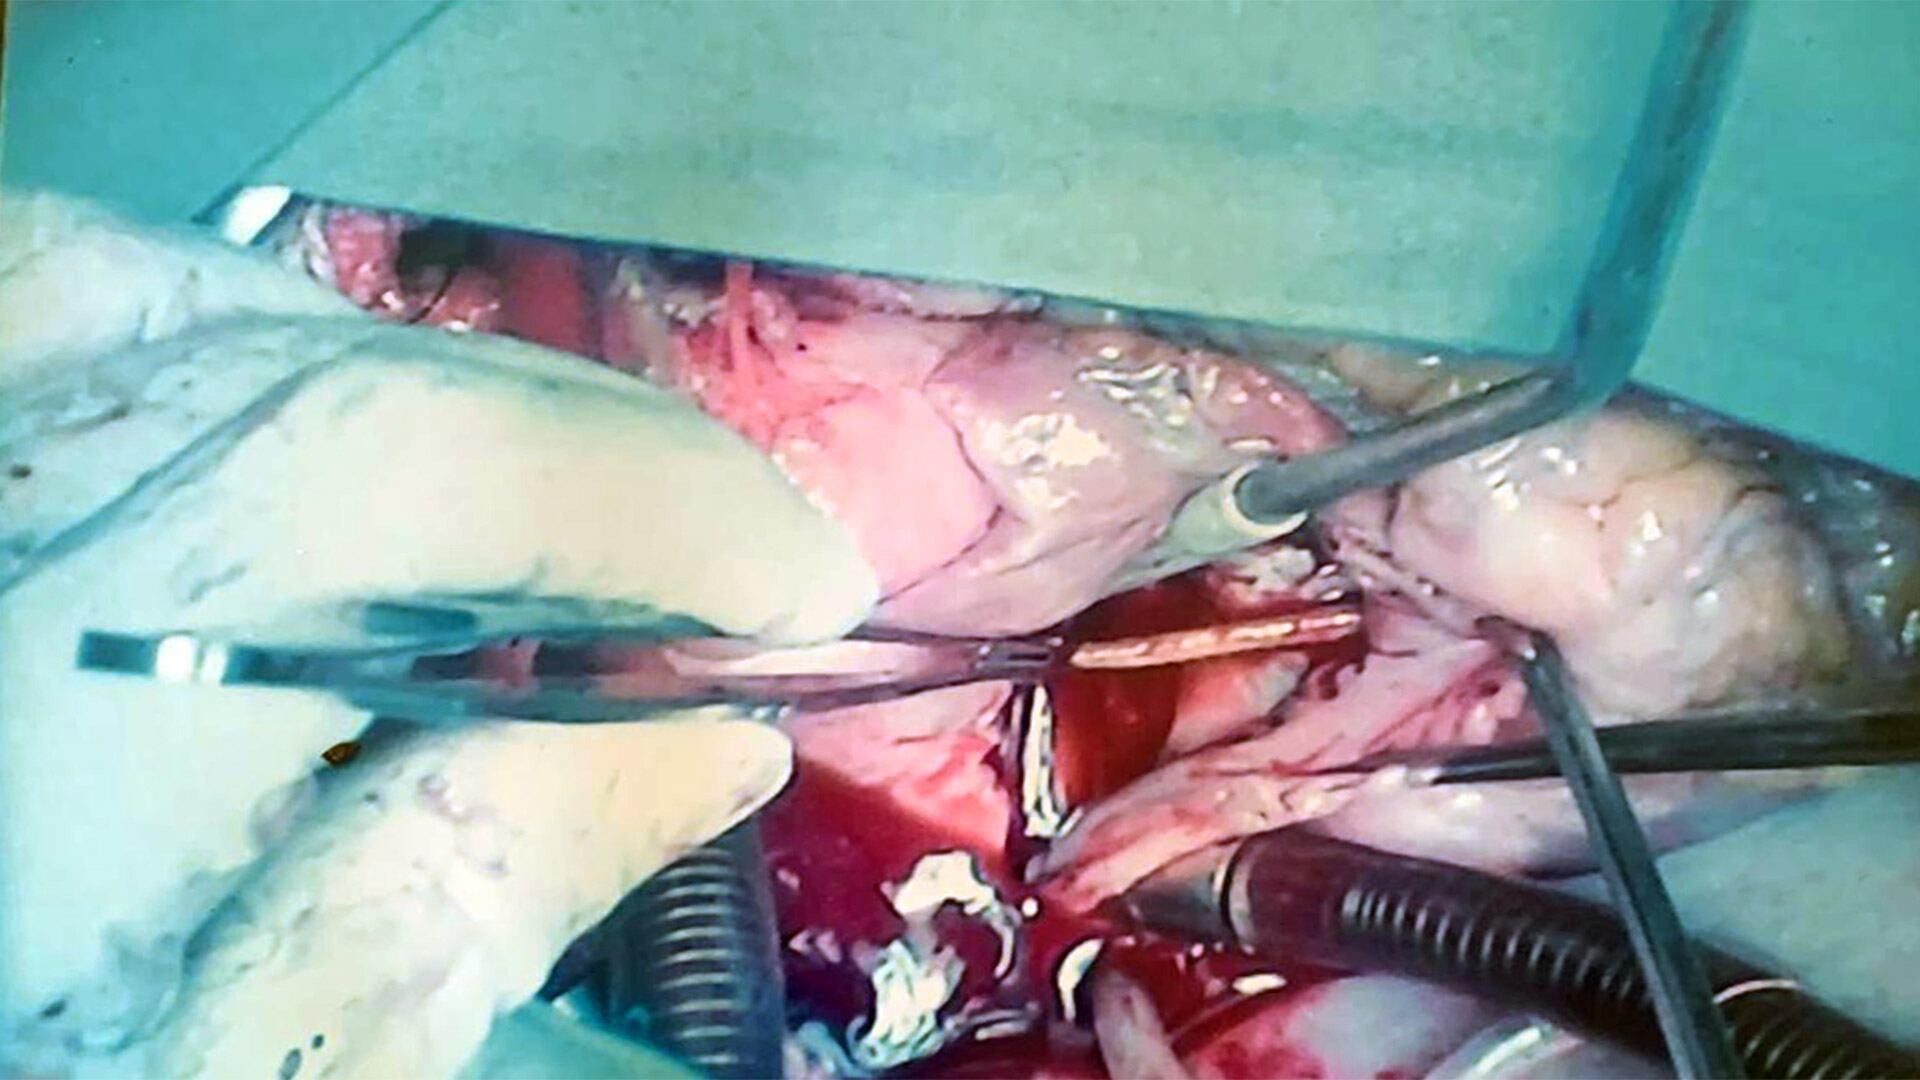

Finalmente, a comienzos de octubre de 2015, el equipo de Cichero decidió intervenirlo. “El plan original era sacarle el catéter por el cuello. Le metimos una pinza de laparoscopía y empezamos a tirar. ¿Qué ocurría? Tirábamos y se le daba vuelta el corazón. Hasta ahí, nosotros pensábamos que era un plástico. El plástico, si vos tirás, se dobla. En ese mismo momento tomamos la decisión de abrirle el tórax. Yo lo lamentaba: ‘Un muchacho tan joven y hay que abrirlo para sacarle un catéter…’. Todo el procedimiento duró seis horas”, cuenta el cirujano.

Cuando Horacio despertó de la anestesia, Cichero le dio la noticia. “Lo que tenías es una cosa única”, le dijo. Al ver el escarbadientes, el correntino no supo qué contestarle. “Lo primero que pensé es dónde me lo pude haber tragado. Hay dos o tres posibilidades; pero todavía tengo mis dudas…”, dice entre risas. Una década después, aquel hombre que vivió con un palillo de madera en el corazón sigue sin secuelas. “Jamás volví a pisar un hospital —asegura, orgulloso—. Soy un afortunado. Me regalaron diez años de vida que estoy aprovechando al ciento por ciento”.